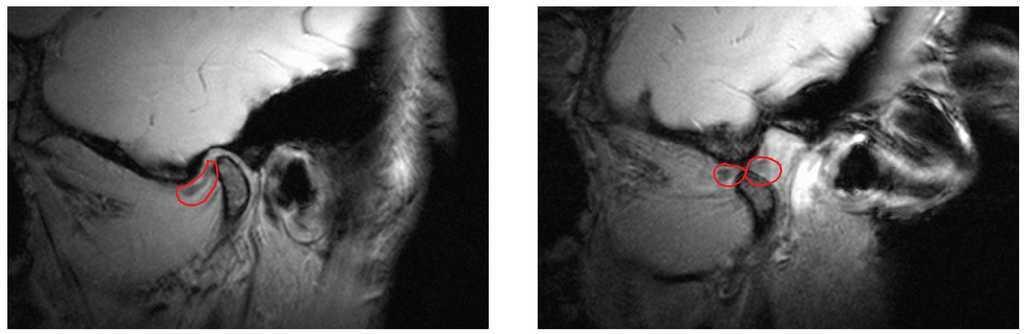

Desplazamiento discal anterior con reducción (fig. 7)

Figura 7. Desplazamiento discal anterior con reducción (disco enmarcado en rojo) (izquierda: boca cerrada, derecha: boca abierta). Este tipo de desplazamiento se caracteriza por chasquidos al abrir y cerrar la boca. La apertura y el cierre no suelen ser dolorosos.

En este caso, con la boca cerrada, el disco se coloca por delante del cóndilo y vuelve a su posición normal al abrir la boca. Es frecuente percibir un chasquido al abrir o cerrar la boca. Aunque este cuadro no necesita forzosamente un tratamiento, puede ser útil reducir el desplazamiento discal antes de una rehabilitación oral previamente programada (por ejemplo con una prótesis híbrida). Para ello se confecciona una férula en protrusión, libre de chasquidos y, más adelante, se estabiliza la nueva posición mandibular mediante la prótesis. Sin embargo, este procedimiento no es adecuado para pacientes que no necesiten una prótesis de al menos una arcada completa. La indicación para reducir el desplazamiento discal se debe evaluar de forma especialmente crítica en pacientes asintomáticos que padecen el desplazamiento discal anterior con reducción desde hace tiempo y que ya se han adaptado a la situación.